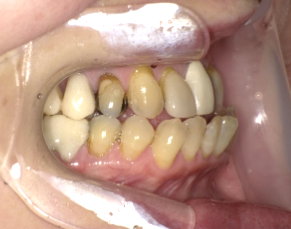

Before Photo

Before